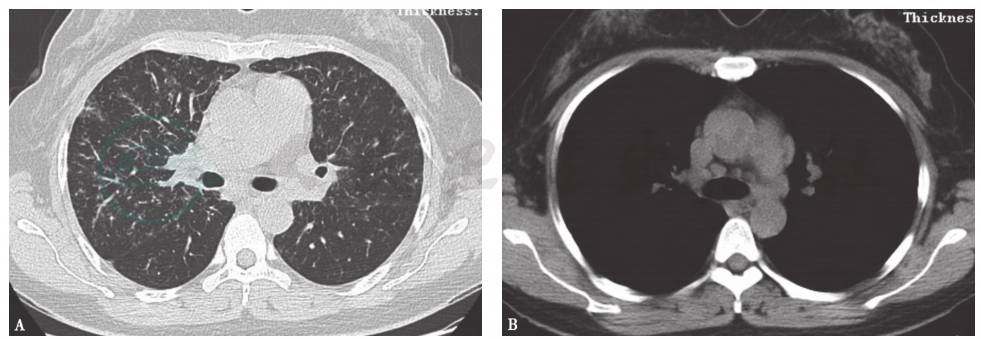

图2 肺泡蛋白沉积症胸部CT表现

男性患者,55岁,因活动后胸闷、气喘5年入院。胸部CT示两肺多发磨玻璃影,地图样分布,其内见铺路石征。行支气管镜检查,支气管肺泡灌洗液及病理符合PAP

图4 结节病胸部CT表现

女性患者,45岁,因活动后气喘1年余入院。胸部CT提示沿淋巴管分布的小结节影累及叶间裂,小叶间隔增厚(A);纵隔淋巴结肿大且不具有融合倾向(B)。肺功能检查示通气功能基本正常,弥散功能轻至中度降低。支气管镜检查右肺支气管黏膜以及中叶TBLB病理示支气管黏膜组织部分区见上皮样肉芽肿形成,并可见多核巨细胞反应、肉芽肿性病变,抗酸染色、GMS染色、PAS染色均阴性